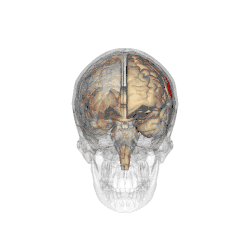

Functional magnetic resonance imaging (fMRI) scans of the brains of subjects exposed to thirty-five hours of sleep deprivation indicate that sleep deprivation is related to increases in prefrontal cortex and parietal lobe activation during tasks that combine verbal learning and arithmetic. This is particularly apparent in the right hemisphere. In non-sleep-deprived people involved in verbal learning and arithmetic tasks, the anterior cingulate cortex and the right prefrontal cortex are active. Following sleep deprivation, there is increased activation of the left inferior frontal gyrus and the bilateral parietal lobes. This information suggests that divided attention tasks require more attentional resources than normally required by a non-sleep-deprived person.[5]

Deficits in cognitive performance due to continuous sleep restriction are not well understood. Studies have looked into physiological arousal of the sleep-deprived brain. Participants, whose total amount of sleep had been restricted by 33% throughout one week, were subjected to reaction time tests. The results of these tests were analyzed using quantitative EEG analysis. The results indicate that the frontal regions of the brain are first to be affected, whereas the parietal regions remain active until the effects of sleep deprivation become more severe, which occurred near the end of the week. EEG and ERP analysis reveals that activation deficits are more apparent in the non-dominant hemisphere—than in the dominant hemisphere.[11]

Lack of sleep changes how genes are expressed and interferes with neurobiological functions that are necessary for cognitive function. Research indicates a decline in the expression of proteins that are essential for memory consolidation and synaptic plasticity, including CREB and PKCγ. These molecular abnormalities damage the cerebellum and hippocampus, which results in deficiencies in long-term memory functions and spatial working memory. Chronic sleep deprivation also raises the brain's amyloid-beta aggregation, which is linked to neurodegenerative diseases like Alzheimer's. Impaired clearance mechanisms during reduced sleep worsen this neurotoxic environment. Neuroimaging studies also show a shift of cognitive resources, which decreases activation in the prefrontal cortex and parietal lobes and increases activation in areas like the thalamus. However, this compensating strategy is not enough to sustain the best possible cognitive function throughout extended periods of wakefulness.[61][62]